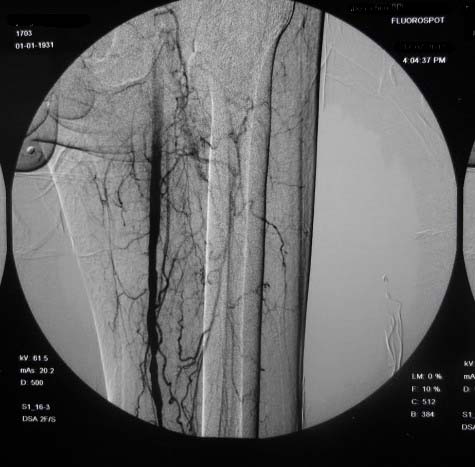

右下肢:

造影方法:取仰卧位,在局麻下,经右股动脉入路,采用改良seldingers技术,置入5f cobra导管于左髂外动脉行dsa,采集速度为2幅/秒,注射速率为6ml/秒,分节段造影;再将导管采用成襻技术放置于右侧髂外动脉,采用左侧同样的方法行dsa,术毕拔管、压迫止血约15分钟,包扎后嘱返病房,术后右足背动脉可扪及搏动。

右侧股浅动脉上、中段多处狭窄,下段闭塞。左侧股浅动脉多处狭窄,国动脉起始部狭窄。可以用球囊扩张配合动脉内溶栓或股浅动脉支架置入。多为糖尿病所致。

双侧股动脉及腘动脉多发狭窄,右股动脉下段闭塞并侧支形成。病变较广泛,球囊可试试,如病人经济不好,最好还是以药物治疗为主。个人意见。